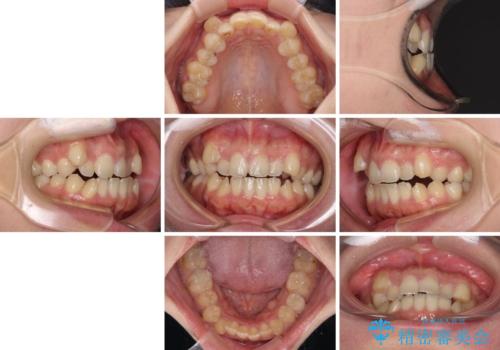

- 八重歯と上下前歯のでこぼこを気にして来院された患者様です。

上下前歯部叢生のスペース獲得のため、上下顎左右小臼歯各1歯(計4本)と全ての親知らずを抜歯して、矯正治療を行うこととしました。

八重歯とは別に上下前歯の隙間という問題もありました。こちらは舌突出癖によるものと考えられたため、舌のトレーニングをしっかりと行っていただきました。